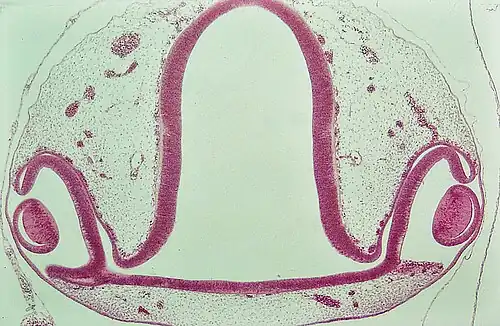

Oogbeker met lensaanleg. Kippenembryo (H&E-kleuring) -